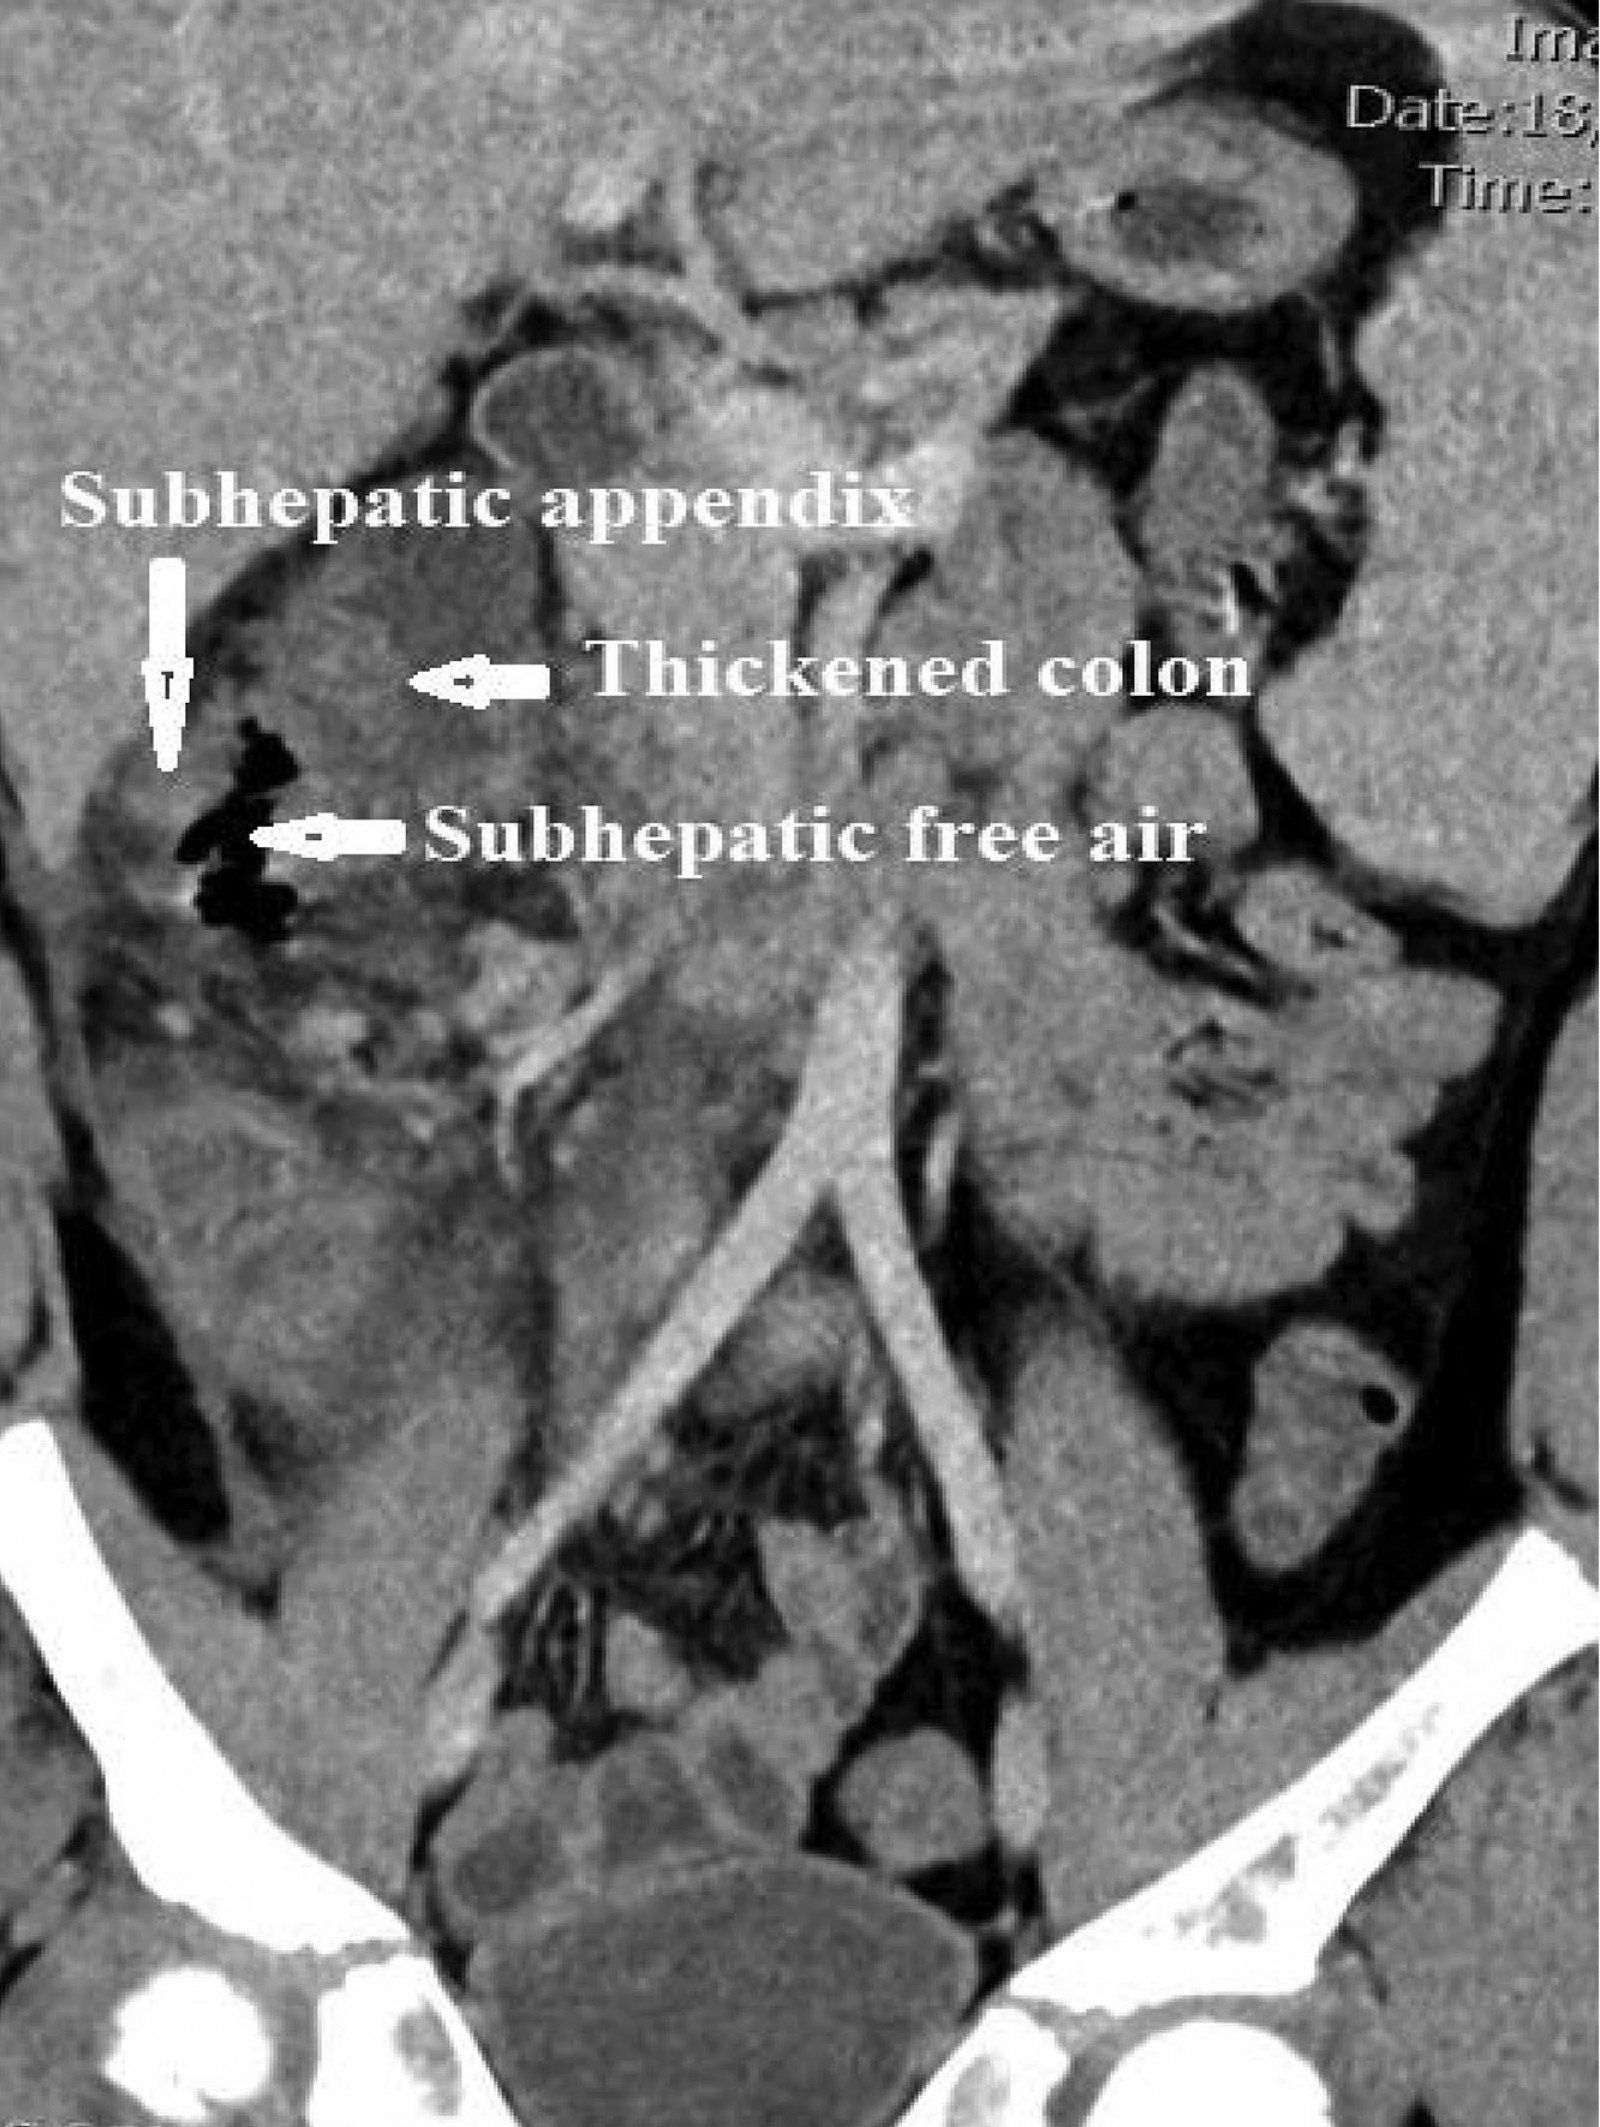

Considering the severity of symptoms and the presence of possible peritonitis, a CT scan of the abdomen and pelvis was performed. The scan showed a markedly thickened, hypoechoic tubular structure medial to the inferior edge of the liver, located retrocaecally (Fig1). The adjacent small bowel loops, hepatic flexure and caecum were thickened (Fig2). The CT scan also demonstrated localised extraluminal gas in the subhepatic region, consistent with perforation. An emergency laparotomy revealed a perforated, gangrenous appendix. The patient’s recovery period was uneventful, and he was discharged on the fourth day after surgery.

Figure 2: CT scan showing extraluminal gas indicative of localised perforation from complicated subhepatic appendicitis and secondary thickening of the adjacent ascending colon.